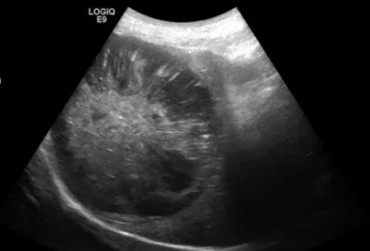

Zarażenie psa pasożytem nicieniem Dirofilaria immitis – opis przypadku

W artykule opisano przypadek dirofilariozy u psa wywołanej D. immitis. U badanego pacjenta stwierdzono patognomiczny obraz zmian w badaniu rentgenowskim i ultrasonograficznym układu sercowo-naczyniowego.